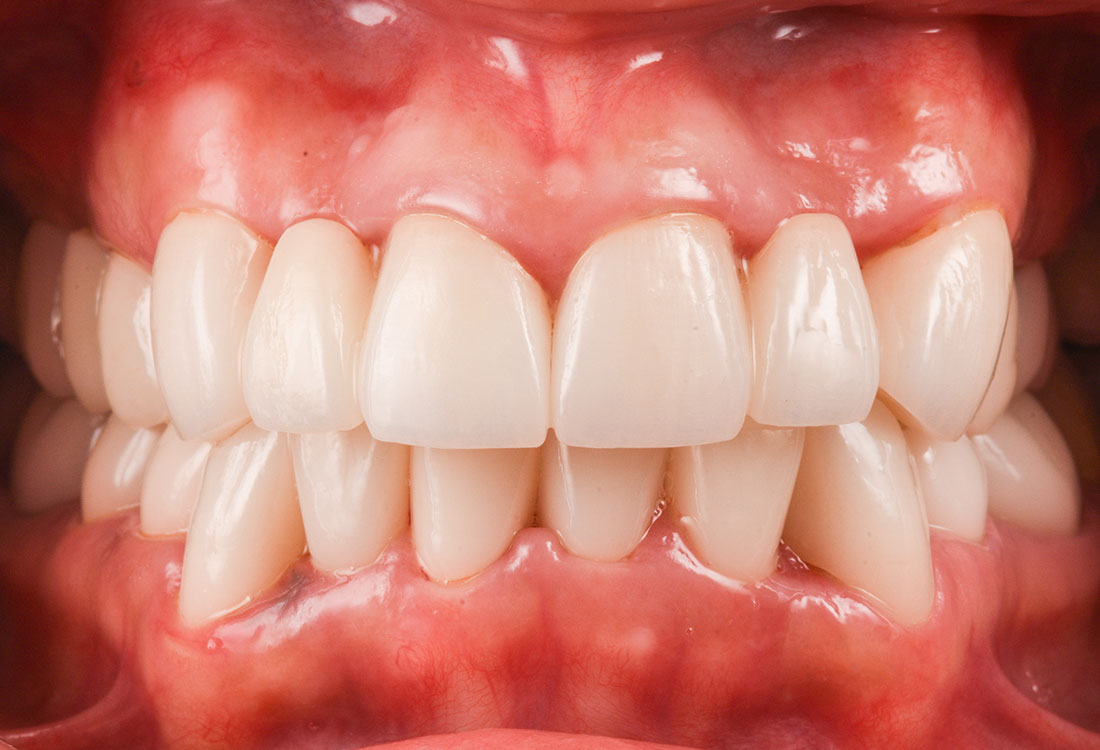

治療後

今回は前歯をグラデーションカラーのジルコニア、奥歯をセレックで治療しました。

見た目の美しさのポイントになるスマイルラインも整っています。